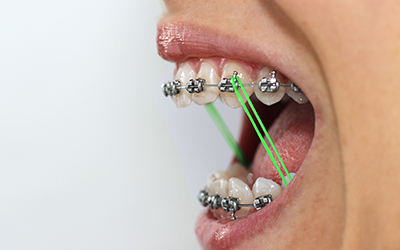

Occlusal trauma can silently damage healthy teeth, and understanding its causes and treatments helps protect long-term oral health.

Proper bite alignment supports efficient chewing, clear speech, and long-term tooth protection by ensuring balanced pressure across the teeth and jaw.